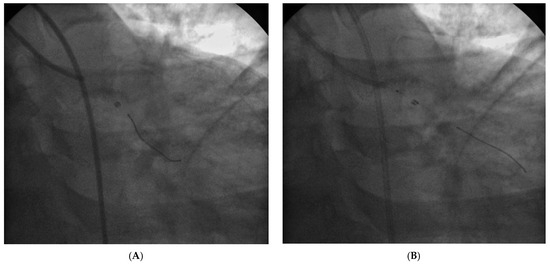

Der 70-jährige Patient wurde uns zugewiesen zur stationären kardialen Rehabilitation bei St. n. mechanischem Aortenklappenersatz wegen schwerer degenerativer Aortenstenose.[...]